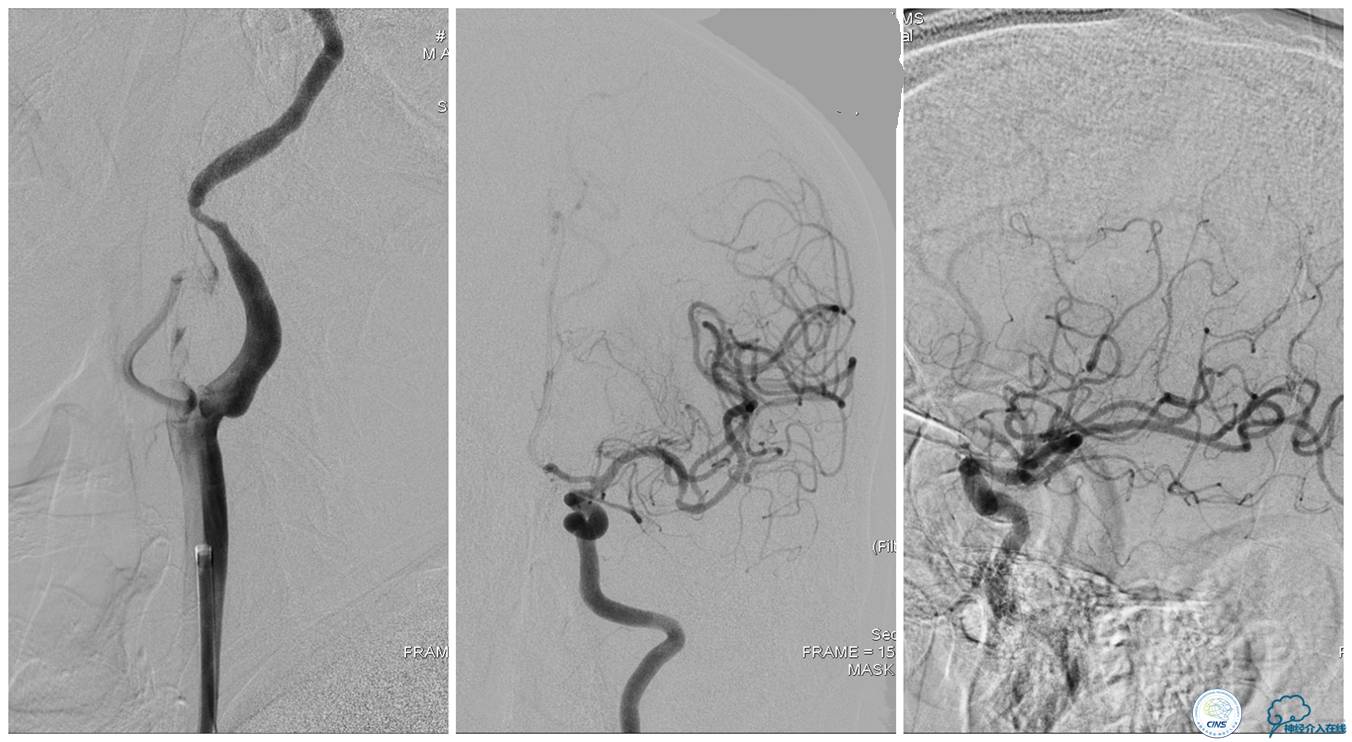

▼21:27穿刺成功,TOT 297min。左侧颈总动脉末端、颈内动脉起始部及颈外动脉起始部长条状血栓形成,随血流晃动,同侧大脑中动脉、大脑前动脉显影良好。

▼选用NAV 6 7.2 mm远端保护装置置于左侧颈内动脉C1段末端,将8F Gulding先后置于颈总动脉及颈内动脉开口部,50 ml注射器反复抽吸,抽出大量血栓。

▼颈总动脉及颈内动脉血栓抽吸完全,远端血流较前好转,TICI 3级。